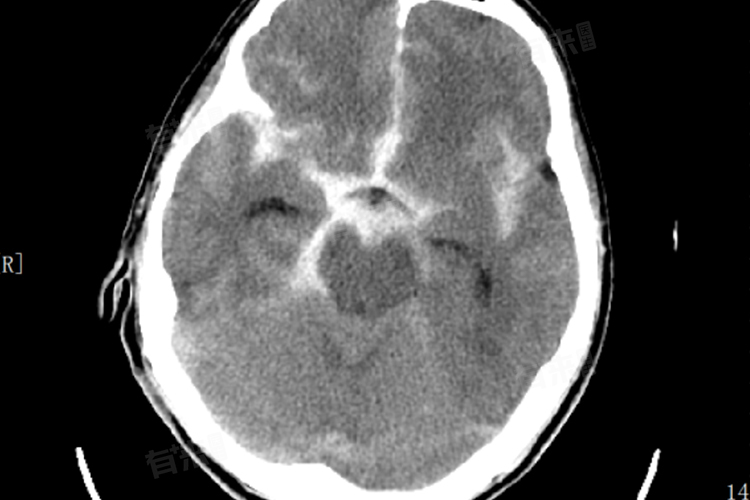

1、CT扫描高密度影:在急性期,头颅CT扫描是检测蛛网膜下腔出血较常用且快捷的方法。当发生出血时,在大脑周围的蛛网膜下腔中会出现高密度区域,这是因为血液积聚形成了对比度较高的影像。

2、脑室系统内血液积聚:如果出血量较大或持续时间较长,血液可能会扩散至脑室系统内,导致脑室内积血。这种情况下,在CT图像上可以看到脑室内部出现不规则的高密度影,这不仅表明出血严重,还可能提示存在脑积水的风险。

3、脑沟增宽与模糊:正常情况下,大脑表面有许多细小的沟回结构,这些结构在CT图像上表现为线状低密度区。然而,在蛛网膜下腔出血患者中,由于血液填充到这些脑沟中,使得原本清晰可见的脑沟变得模糊不清,并且看起来比平时更宽。